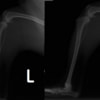

■ 症例24 キャバリア 7か月

左右膝蓋骨内方脱臼(左:グレードⅣ 右:グレードⅢ)

以前から左右後肢の跛行が認められ、整形外科学的検査・レントゲン検査により左右の膝蓋骨脱臼が認められた。症状が重度である左膝の膝蓋骨脱臼整復術を行った。外科手技は縫工筋及び内側広筋の解放、脛骨粗面の外側転位、滑車ブロック形造溝術、内外側関節方の縫縮を実施した。術後一か月時点で、左の膝蓋骨は安定しており経過は良好である。

本症例は成長期における重度の膝蓋骨脱臼であり、術後の再発の可能性もあるため、経過をしっかりと観察していく必要がある。また、今回手術を実施していない右膝に関しても経過を観察し、手術を検討していくこととする。